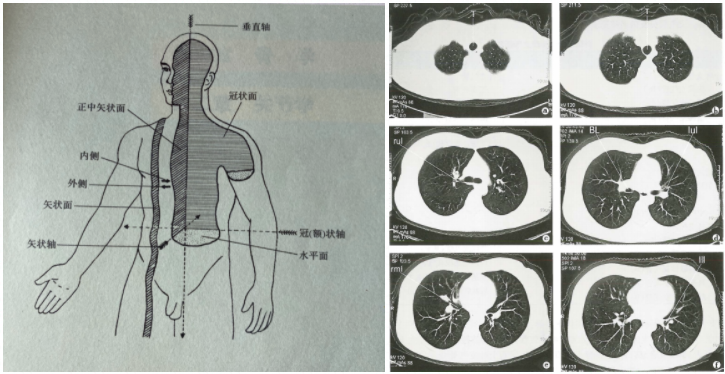

CT是X射线计算机层流成像的缩写。从全名中可以看出,CT也是一种X射线成像技术。 CT和普通X射线之间的最大区别是“身体层”一词。 X射线是无数的层,添加了图像,而CT是真正的层析成像图像,也就是说,扫描零件的多个级别是分别成像的 - 例如,您是法式面包(或者是从中的肉条)一家火锅餐厅)硬又长。我们想看看您内部的外观,因此我们有一台机器将您从头到脚切成薄片,以便您可以看到它。每个薄截面是什么样的?目前,每个级别的图像都没有其他级别的影响,并且可以清楚地观察到单个级别的组织结构和病变。

CT成像是比X射线更高分辨率的数字复制图像(特定于不同设备和处理技术的不同像素)。同时,CT成像的密度值是可量化的。高,中和低密度不仅可以用来描述图像,而且还可以直接描述密度的CT值。 CT通常使用水平轴断层扫描(即减半,法式面包的水平是什么水平),因此您通常会看到的CT膜总是一一偏椭圆形图像(右图如下图所示)。但是,在头部,脸部或颅骨CT检查期间,有时是冠状扫描(垂直分为两半的大型平面)是躺下并平坦的零件,以便每次都应该切割头部,剪切方向并清楚地看到。

图片的左侧显示了人体的轴和表面,图片来自Jilin Science和Technology Press Human Anatomy。图片的右侧显示了正常的肺窗口CT,该肺部CT与医学成像截获。

直接使用不同组织厚度和密度进行成像的CT称为CT扫描,通常可以在几分钟内完成检查。使用对比剂来帮助成像的CT称为CT增强。考试时间稍长。根据考试现场和增强技术,可能需要几分钟到半小时。随着CT技术的发展,“切片”的厚度越来越薄。应用螺旋CT后,可以将成像视为连续且均匀的扫描。在患者检查后,可以取出存储的膜并选择某个部分进行打印。在使用最新成像系统的医院中,医生可以直接观察到计算机上成像系统中患者的CT扫描的每个级别,如果需要进一步操作,将进行进一步的操作。图像处理也可以在原始扫描图像上进行,而无需患者进行次要检查。

CT成像具有许多级别,高分辨率和相对较高的价格。它的价格通常与扫描位置有关。例如,2021年最大的三级医院的高分辨率螺旋CT扫描是198元人民币,胸部很高。分辨率的螺旋CT扫描为378元,比普通的X射线更经济。当医生在X射线和CT之间进行选择时,他将权衡患者的病情,病变位置,经济状况等。因此,当X射线检查可能“不清楚”时,可能建议患者接受CT检查一个步骤,不仅可以减少X射线吸收(即避免了生产线的次要饮食),而且不会延迟由于反复检查而引起的诊断和治疗。